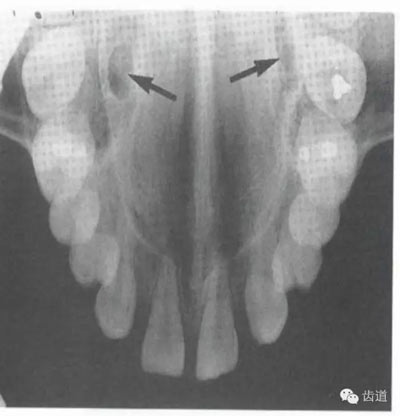

8)頦嵴:

在正中聯(lián)合的兩旁,各有一致密影像帶,呈八字形延長至前磨牙區(qū),是頦嵴的影像。

9)內(nèi)斜線:

為自頦嵴斜向上后的致密線條影,至升支前緣消失,位于外斜線之下,走行方向與其一致。